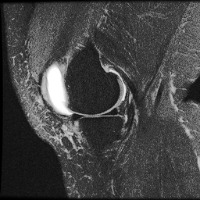

meniscal Computer Vision Project

Medical Diagnostics: Radiologists, orthopedic surgeons, and other medical professionals can utilize the "meniscal" model to accurately identify and classify meniscal lesions in knee MRI scans, thus improving the diagnosis and treatment process for patients with knee-related injuries and conditions.

Sports Injury Prevention and Management: Sports rehabilitation centers and athletic trainers can employ the "meniscal" model for analyzing knee scans of athletes to assess the health of their knees, track any changes over time, and tailor training regimens or treatments to prevent or recover from meniscal injuries.

Pre- and Post-Surgery Evaluation: Surgeons can use the "meniscal" model to analyze the knee scans taken before and after meniscal surgeries to evaluate the efficacy of the surgical intervention and make informed decisions about the patient's further treatment plan and rehabilitation process.